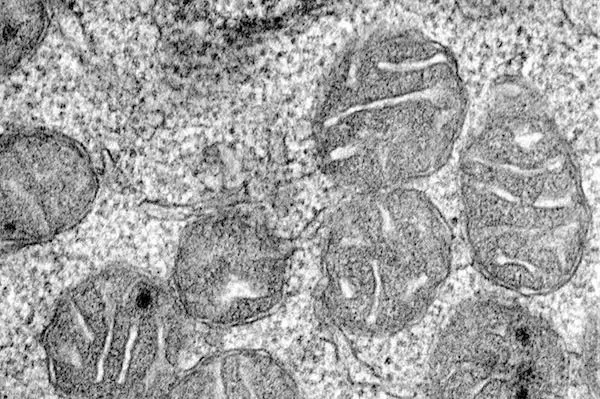

An electron microscope image showing the mitochondria inside an erythroid progenitor, the cell that divides to make red blood cells. This image was taken at 50,000x magnification - 70 of these images lined up side-by-side would equal the diameter of a human hair.

An electron microscope image showing the mitochondria inside an erythroid progenitor, the cell that divides to make red blood cells. This image was taken at 50,000x magnification -- 70 of these images lined up side-by-side would equal the diameter of a human hair.